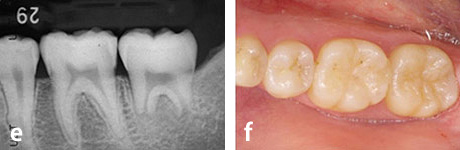

e、f : 移植後6ヶ月